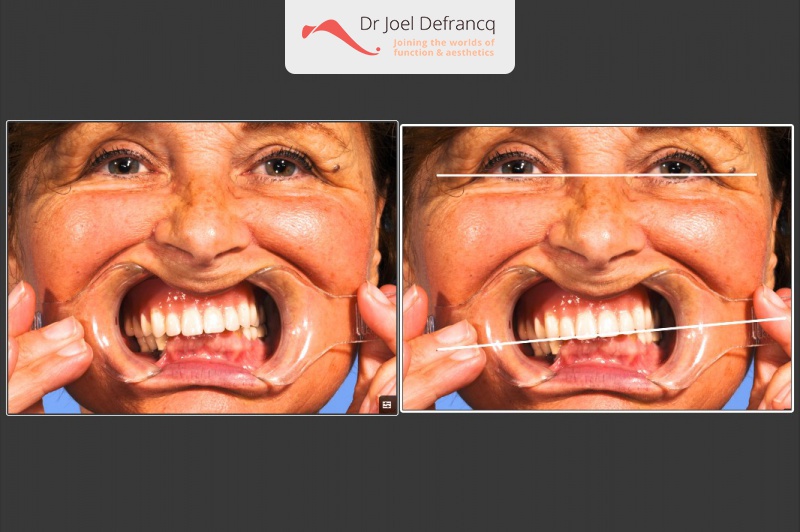

Bessina: "all on four " dentale implantaten

Behandeling tandheelkundige implantaten

- Vaste tanden op implantaten (bovenkaak)

- Vaste tanden op implantaten (onderkaak)

- Zygoma implantaten